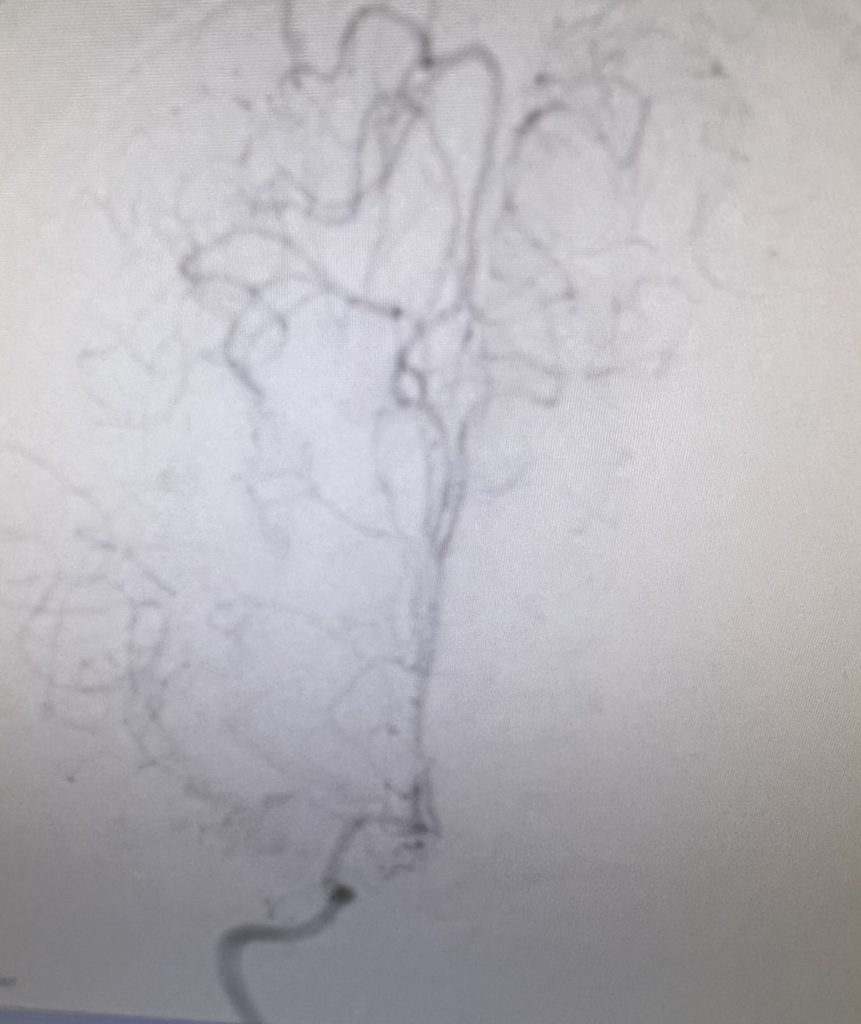

Noninvasive vascular imaging was sufficiently suggestive to warrant conventional digital subtraction angiography, performed by Dr. Brisman and confirming Moya-Moya syndrome (Figures 1). CT Perfusion (Figure 2) showed a decreased transit time of blood to the right hemisphere and the patient was recommended to undergo cerebral revascularization to avert stroke.